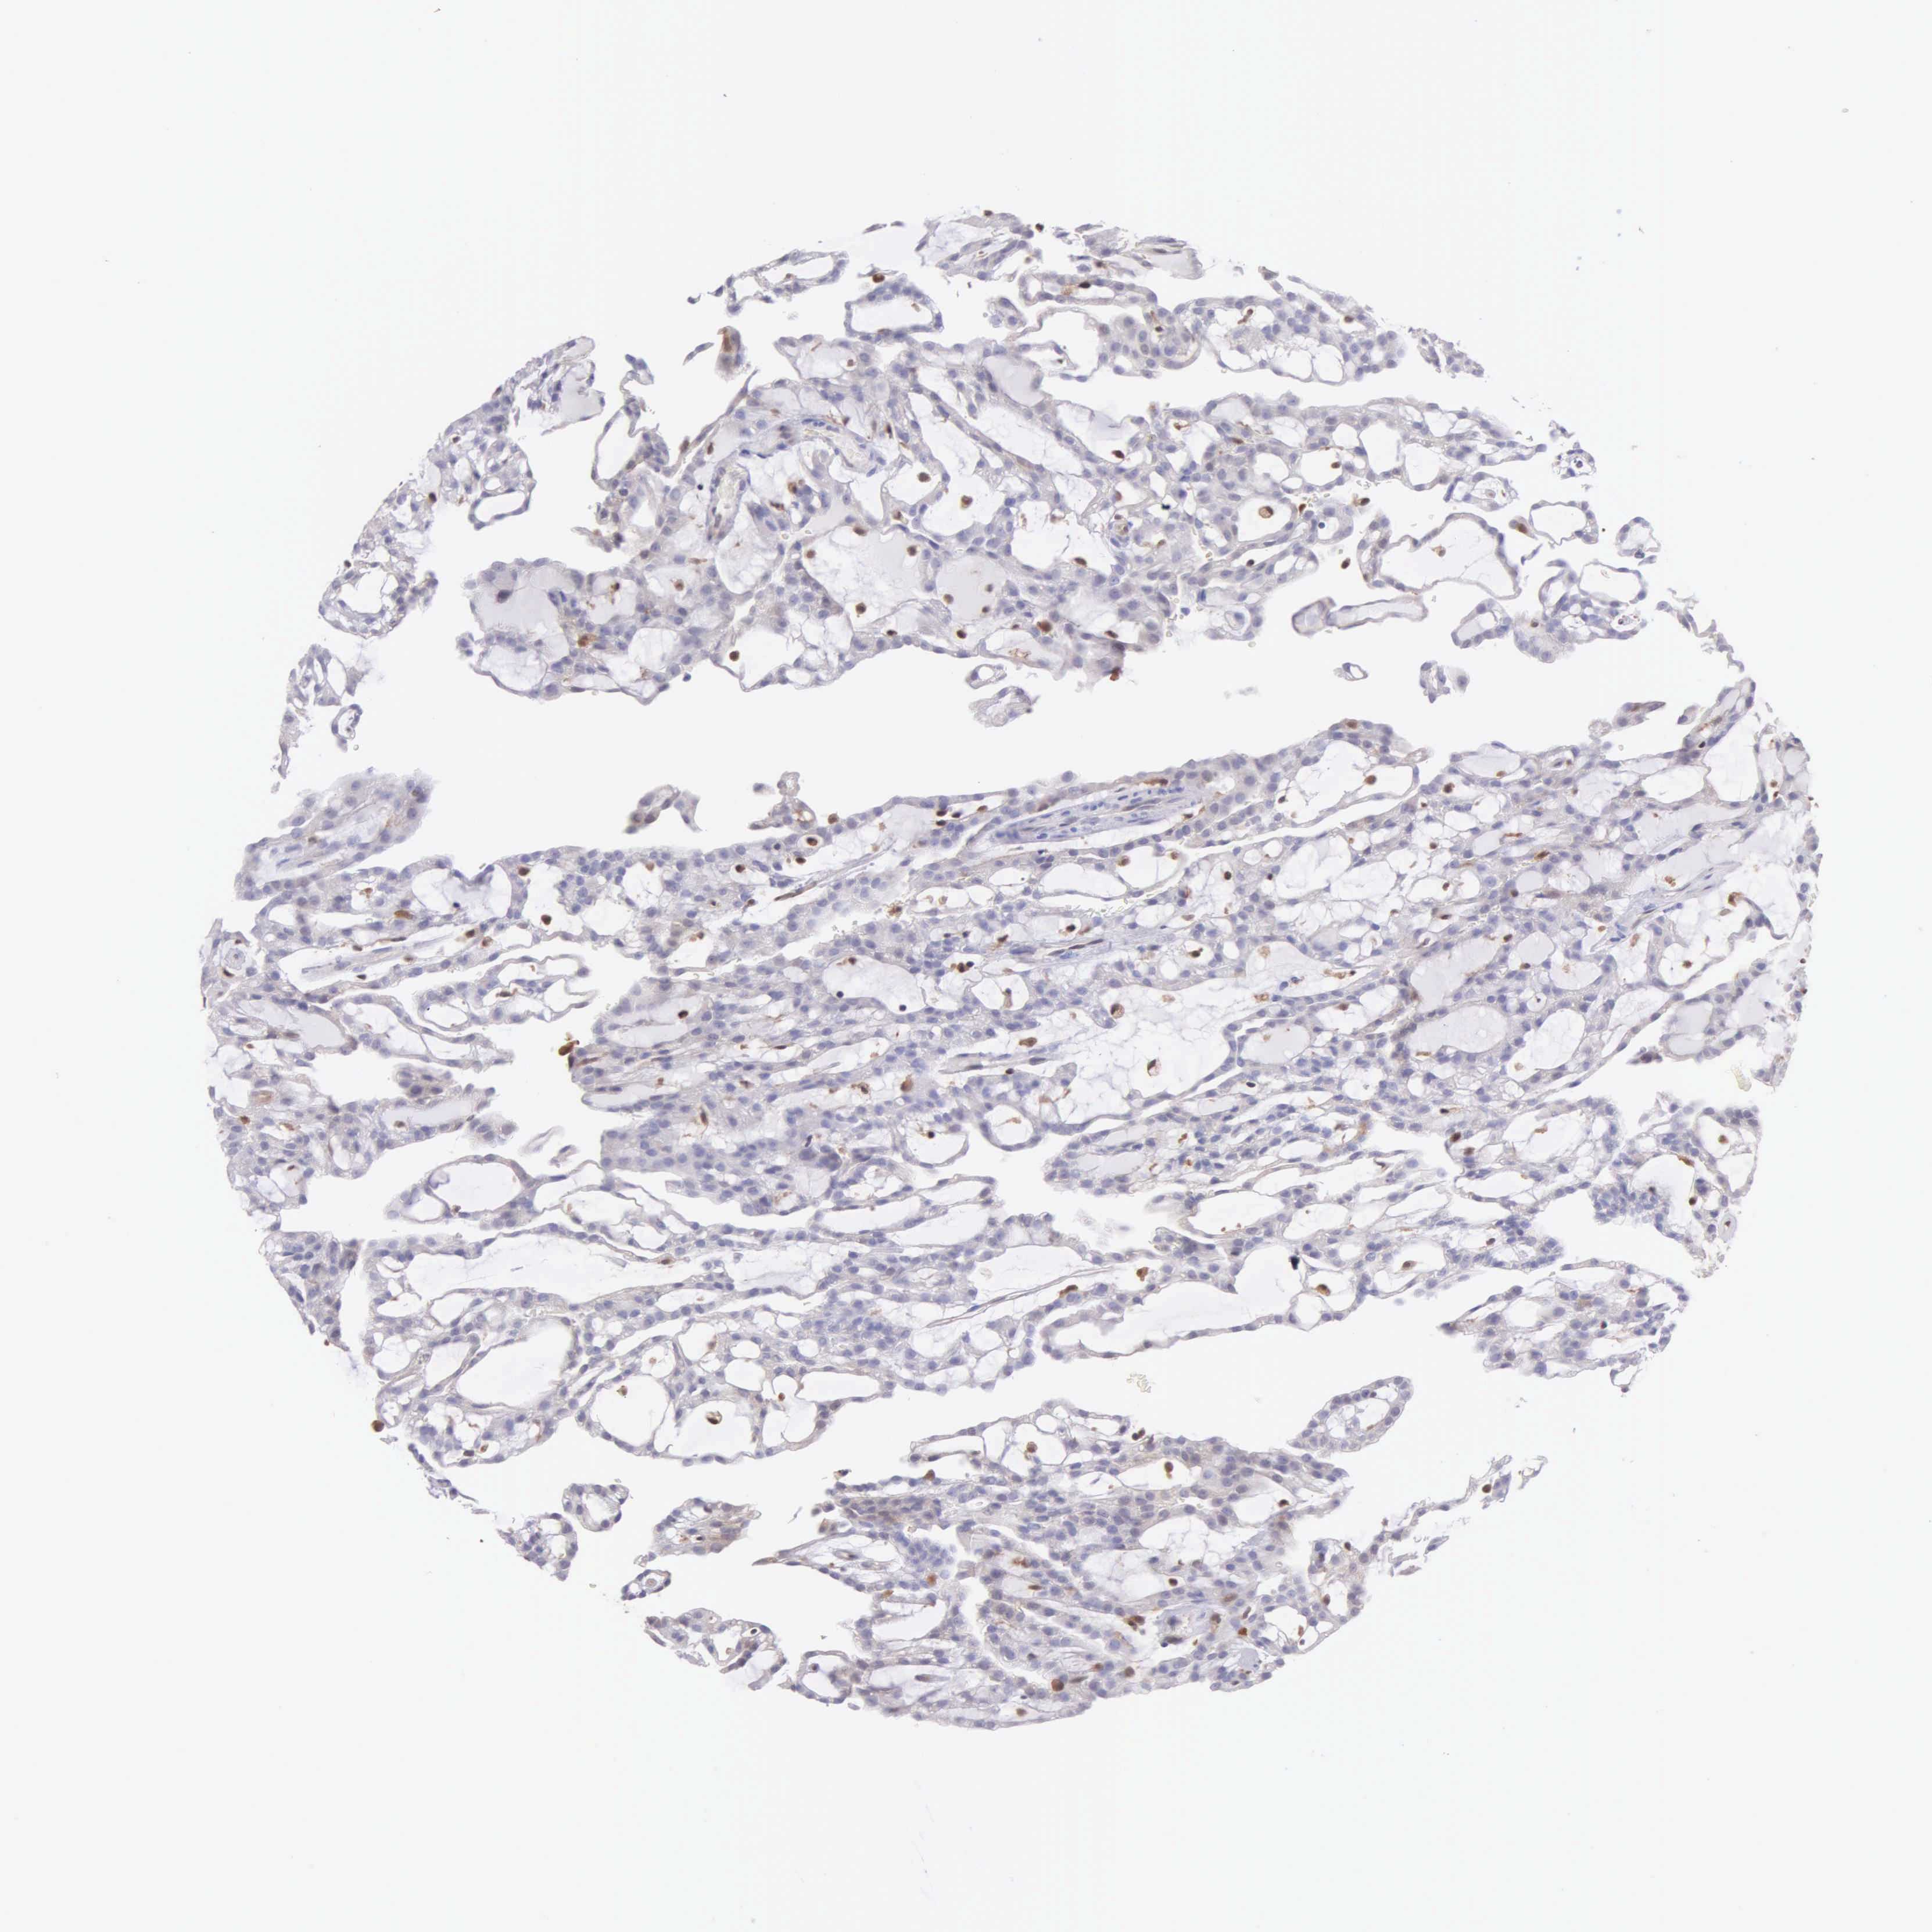

KIDNEY RENAL PAPILLARY CELL CARCINOMA (TCGA) - Interactive survival scatter ploti

The Survival Scatter plot shows the clinical status (i.e. dead or alive) for all individuals in the patient cohort, based on the same data that underlies the corresponding Kaplan-Meier plots. Patients that are alive at last time for follow-up are shown in blue and patients who have died during the study are shown in red.

The x-axis shows the expression levels (FPKM) of the investigated gene in the tumor tissue at the time of diagnosis. The y-axis shows the follow-up time after diagnosis (years). Both axes are complimented with kernel density curves demonstrating the data density over the axes. The top density plot shows the expression levels (FPKM) distribution among dead (red) and alive patients (blue). The right density plot shows the data density of the survived years of dead patients with high and low expression levels respectively, stratified using the cutoff indicated by the vertical dashed line through the Survival Scatter plot. This cutoff is automatically defined based on the FPKM cutoff that minimizes the p-score. The cutoff can be changed by dragging the vertical line or by entering a cutoff value in the square labeled "Current cut-off".

Under the Survival Scatter plot the p-score landscape (black curve; left axis) is shown together with dead median separation (red curve; right axis). Dead median separation is the difference in median mRNA expression between patients who have died with high and low expression, respectively. It is calculated as follows: median FPKM expression of dead patients with high expression - median FPKM expression of dead patients with low expression. This is intended to aid the user in visually exploring custom cutoffs and the associated p-scores and dead median separation.

Individual patient data is displayed and can be filtered by clicking on one or more of the category buttons on the top of the page. Categories describing expression level and patient information include: high, low, alive, dead, female, male and tumor stages. The scale of the x-axis can be toggled between linear and log-scale by clicking on the "x log" button. Mouse-over function shows TCGA ID, patient information and mRNA expression (FPKM) for each patient.

& Survival analysisi

Kaplan-Meier plots summarize results from analysis of correlation between mRNA expression level and patient survival. Patients were divided based on level of expression into one of the two groups "low" (under cut off) or "high" (over cut off). X-axis shows time for survival (years) and y-axis shows the probability of survival, where 1.0 corresponds to 100 percent.

BID is potential prognostic, high expression is unfavorable in Kidney Renal Papillary Cell Carcinoma (TCGA)

Best expression cut offi